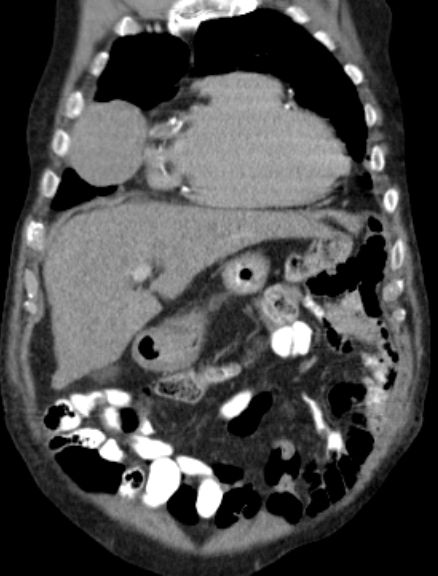

| Thorax | 76-jähriger Mann mit Herzinsuffizienz, Niereninsuffizienz und Pleuraerguss beiderseits.

Das CT zeigt eine intrathorakale Raumforderung rechts ventrolateral.![]() |

| Metastasierung | Lungenmetastasen und Lokalrezidiv 1 Jahr nach Leiomyosarkom der rechten Beckenwand.

![]() | ||